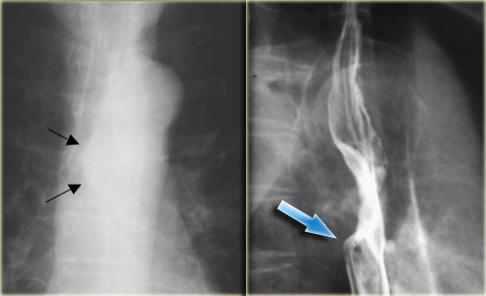

Hẹp thực quản đa ổ là tình trạng ít gặp.

Bảng liệt kê các bệnh lý có thể biểu hiện với hình ảnh hẹp thực quản đa ổ.

Hình ảnh của bệnh nhân mắc pemphigoid lành tính.

Các bóng nước niêm mạc đã dẫn đến hình thành nhiều đoạn hẹp (mũi tên).

Hình ảnh của bệnh nhân mắc ly thượng bì bọng nước lành tính.

Các đoạn hẹp đa ổ (mũi tên) là di chứng của bệnh lý bọng nước niêm mạc.

Bệnh lý bọng nước da lan rộng đã dẫn đến dính ngón tay và co rút.

Nuốt phải chất ăn mòn có thể dẫn đến hình thành nhiều đoạn hẹp thực quản.